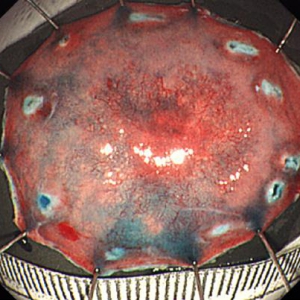

《大腸ESDの実際》

ESDとは内視鏡的に使用可能な高周波メスを使って、粘膜下層のレベルで病変を剥がし取る手技です。当科では、従来の内視鏡治療(EMR)では、一括切除が困難と思われる大腸腫瘍に対して積極的にESDを行っております。体を切開することなく組織も温存できるため、患者の身体的負担が少ない低侵襲医療のひとつです。

大腸ESDは年間約15例ほど行っております。